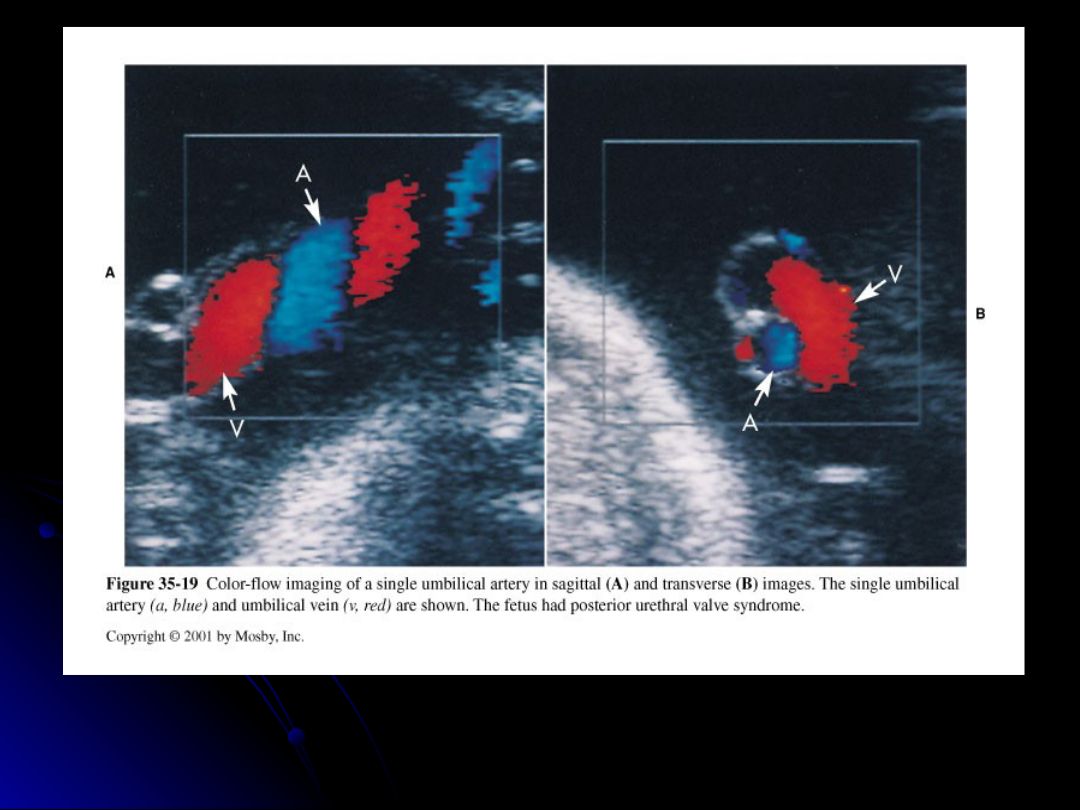

If a single umbilical artery is seen, the sonographer should search for which one of the following?

genitourinary defect